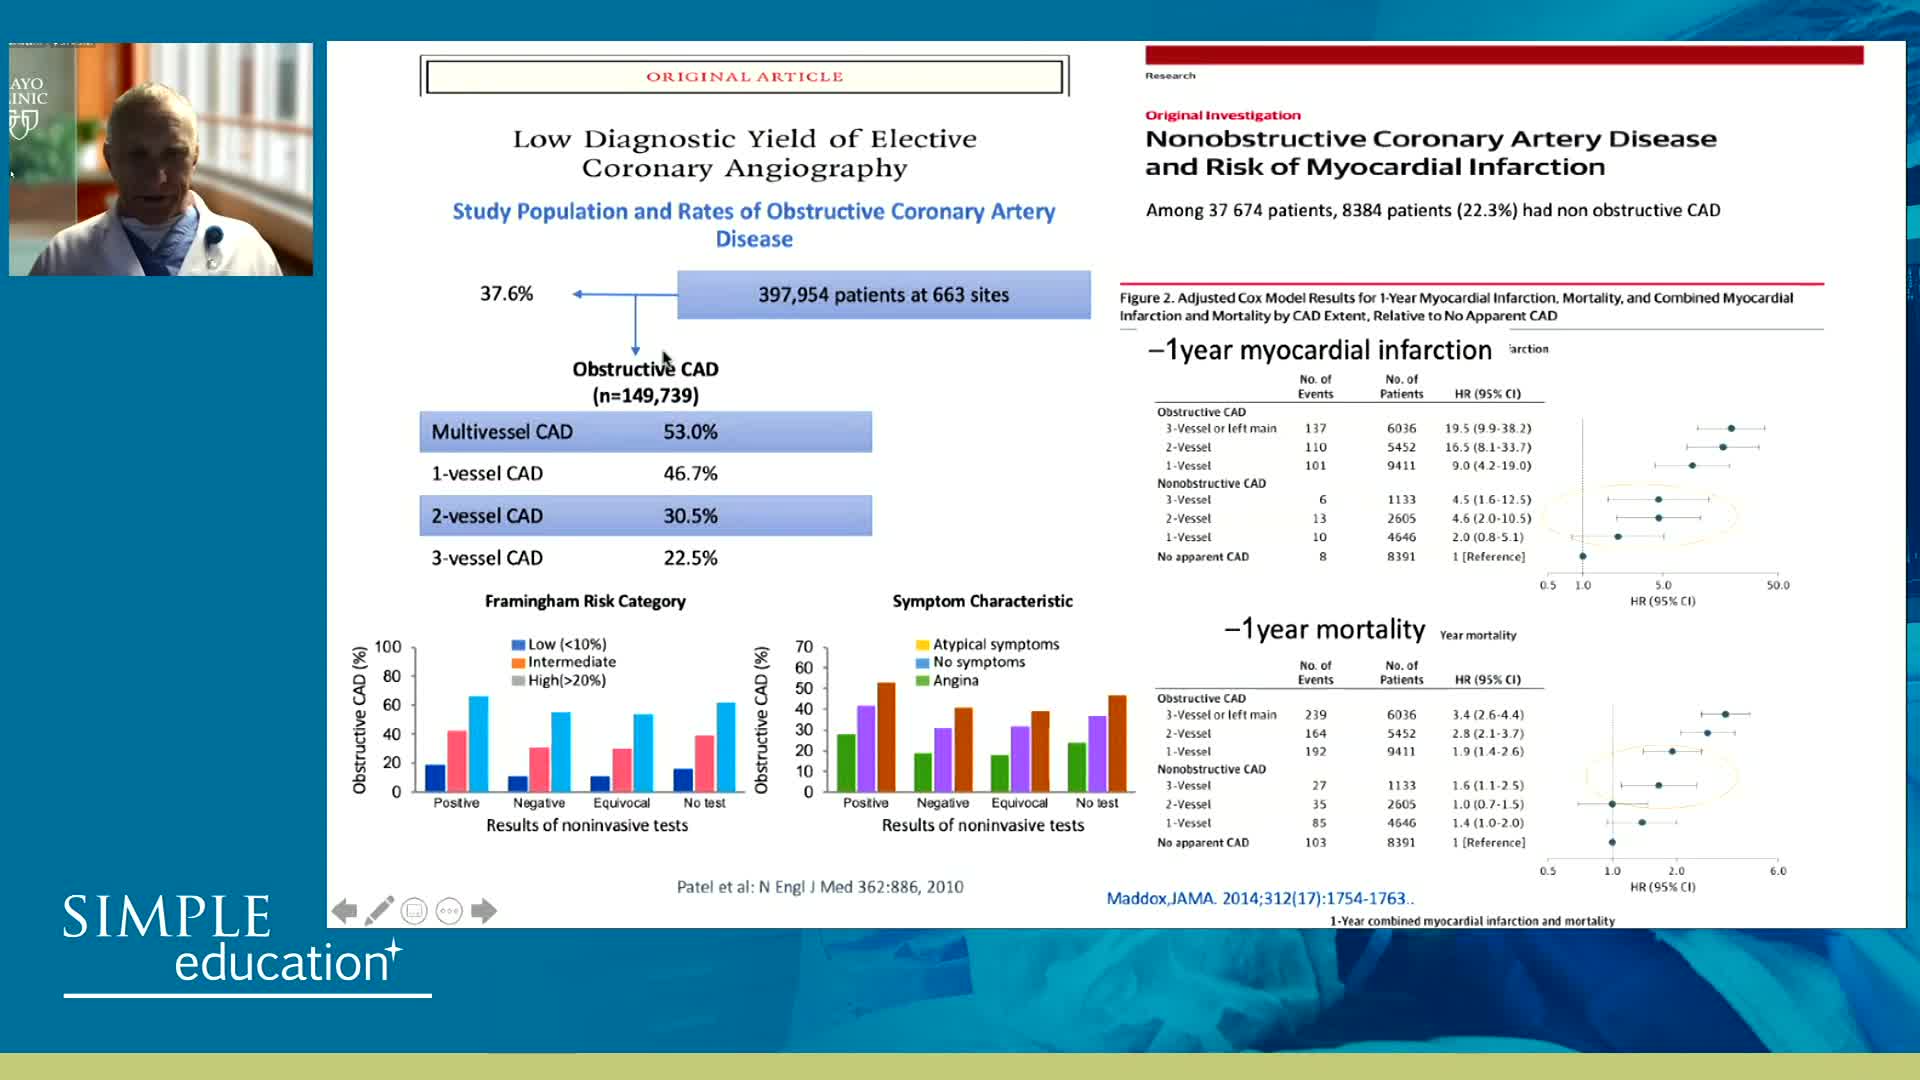

Coronary physiology gate keeper or guide to coronary PCI? Rationale and design of DEFINE-GPS

Revascularisation in stable angina: a contemporary perspective - Dr Rasha Al-Lamee